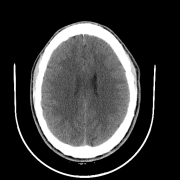

So far we have observed enhanced performance through the SA term. In this subsection, we visually illustrate how this novel term imposes smoothness between attention scores of consecutive slices, leading to more accurate predictions. Figure 2 shows plots of the attention scores assigned by SA-DMIL- and Att-MIL to the slices of three different scans (Fig. S1 in the appendix contains an analogous plot for SA-DMIL-). As expected, introducing the SA loss results in smoother attention weights. Note that the smoothness constraint of SA-DMIL effectively penalizes the appearance of isolated non-smooth attention weights that incorrectly jump over or below the threshold.

We also include visual examples of consecutive CT slices in Fig. 3. In Scan 1, the baseline Att-MIL produces a wrong prediction at scan level. When using SA, the prediction is correct since dependencies between adjacent slices have been learned. In Scan 2, both models produce correct predictions at scan level, but SA-DMIL is more accurate at slice level. This occurs thanks to the SA loss, that turns the attention scores into smoother values and, therefore, avoids random jumps up and down the decision threshold.